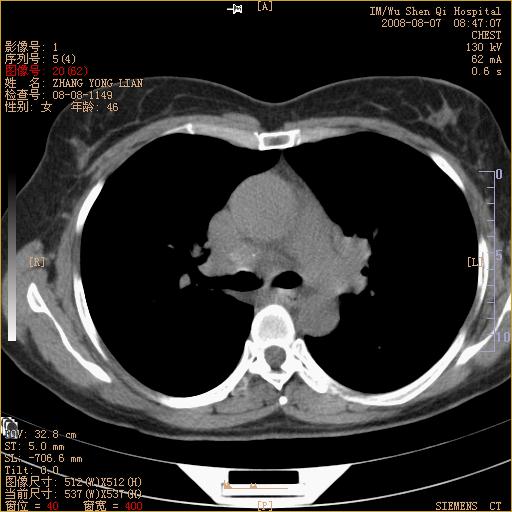

标题: CT15050:女,46岁,咳嗽胸痛一月余 [打印本页]

纵隔窗没发全,左下肺近胸膜处结节。有长毛刺,纵隔淋巴结增大,不排除恶性病变。

考虑肺癌

考虑左肺下叶后基底段周围型肺癌伴纵隔淋巴结转移可能性大。

左下肺ca并纵隔及左肺门区淋巴结转移。

脾脏低密度结节转移不排除。

1)考虑左肺下叶后基底段周围型肺癌伴纵隔淋巴结转移。2)脾内低密度灶,性质待定;不排除转移瘤可能。

考虑左肺下叶后基底段周围型肺癌伴纵隔及肺门淋巴转移。